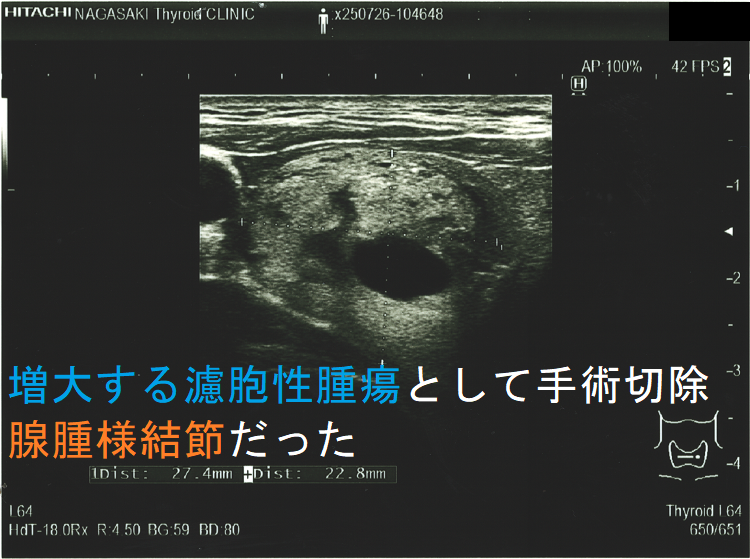

ある意味、腫瘍の増大速度程、悪性の可能性を疑わせる所見は他にありません。急激な速度で大きくなる濾胞性腫瘍は、異常な速度で細胞増殖がおこっています。それは高い確率で甲状腺濾胞癌であると考えざる得ません。(サイズ増大で甲状腺濾胞癌と診断)

- 腺腫様甲状腺腫:14 例(10%);やはり、エコー・細胞診での鑑別が難しいものがありますので

超音波(エコー)画像上、腺腫様結節と甲状腺濾胞性腫瘍は類似しますが

- 被膜があれば甲状腺濾胞性腫瘍ですが、被膜がなければ腺腫様結節[ただし腺腫様結節でも、腫瘍の境界部のハロー(halo:低エコー帯)は、不完全な形で存在します]

- ハローが全周性に認められれば、甲状腺濾胞性腫瘍の可能性が高い。(ただし、ハローの一部途絶、 肥厚等は甲状腺濾胞癌の可能性を考えます。)

- 中心に達する栄養血管がなければ腺腫様結節ですが、あれば甲状腺濾胞性腫瘍・腺腫様結節いずれの可能性もあります。